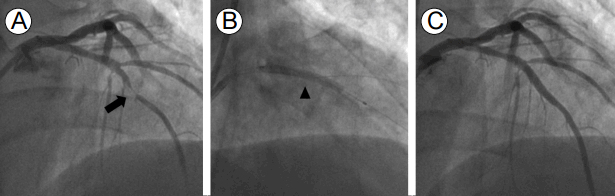

관상동맥협착증에 의한 불안정협심증이 강력히 의심되어 관상동맥조영술을 시행하였고, 좌전하행동맥(left anterior descending artery) 중위부의 심한 협착이 확인되어 약물용출성 스텐트를 사용한 경피적 관상동맥성형술(percutaneous coronary intervention, PCI)을 시행하였다(Fig. 3). PCI 이후 흉통은 소실되었으며 고혈압, 고지혈증과 당뇨병에 대한 약물 치료에 더해 aspirin과 clopidogrel을 병행한 이중 항혈소판 치료(dual antiplatelet therapy)를 유지하였고, 1년이 경과 후 clopidogrel만 중단하고 나머지 약물 치료를 유지 중이다.

Figure 3.

Percutaneous coronary intervention with a drug-eluting stent (DES): (A) a tight stenosis of the middle portion of left anterior descending artery (arrow); (B) DES deployment in the lesion (arrowhead); (C) successful final result.